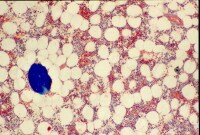

Wnt signaling plays a key role in the fate of mesenchymal stem cells (MSCs), which are the progenitor cells of mature bone-forming osteoblasts.[26] MSCs have the capability to differentiate into adipocytes, chondrocytes, neurons, and muscle cells, as well as into osteoblasts.[27] Certain Wnt signaling pathways promote the differentiation of MSCs along the osteoblast lineage. The emerging details about the specific molecules involved in the Wnt pathway have improved the understanding of bone metabolism and led to the development of new therapeutic targets for metabolic bone diseases.